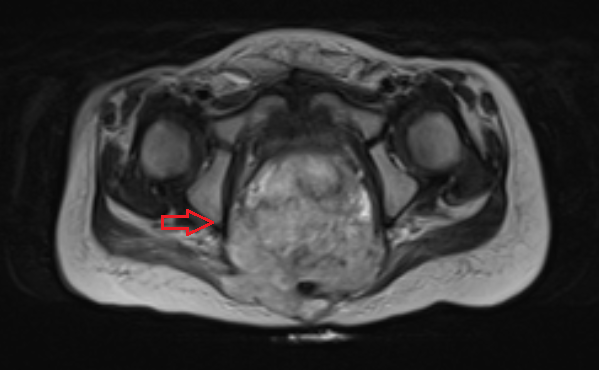

На данном УЗИ представлена больная с симптомом Тернера 45ХО матка нормальных размеров, цервикальный канал норма, полость матки норма, матка с нормальными пропорциями тело/шейки, яичники тяжисты без созревающих фолликулов.

МРТ, Т2-взвешенные последовательности демонстрируют тяжистые матку и яичники ( стрелки ), короткое влагалище ( V ), расположенное между прямой кишкой ( R) и уретрой (Ur ).